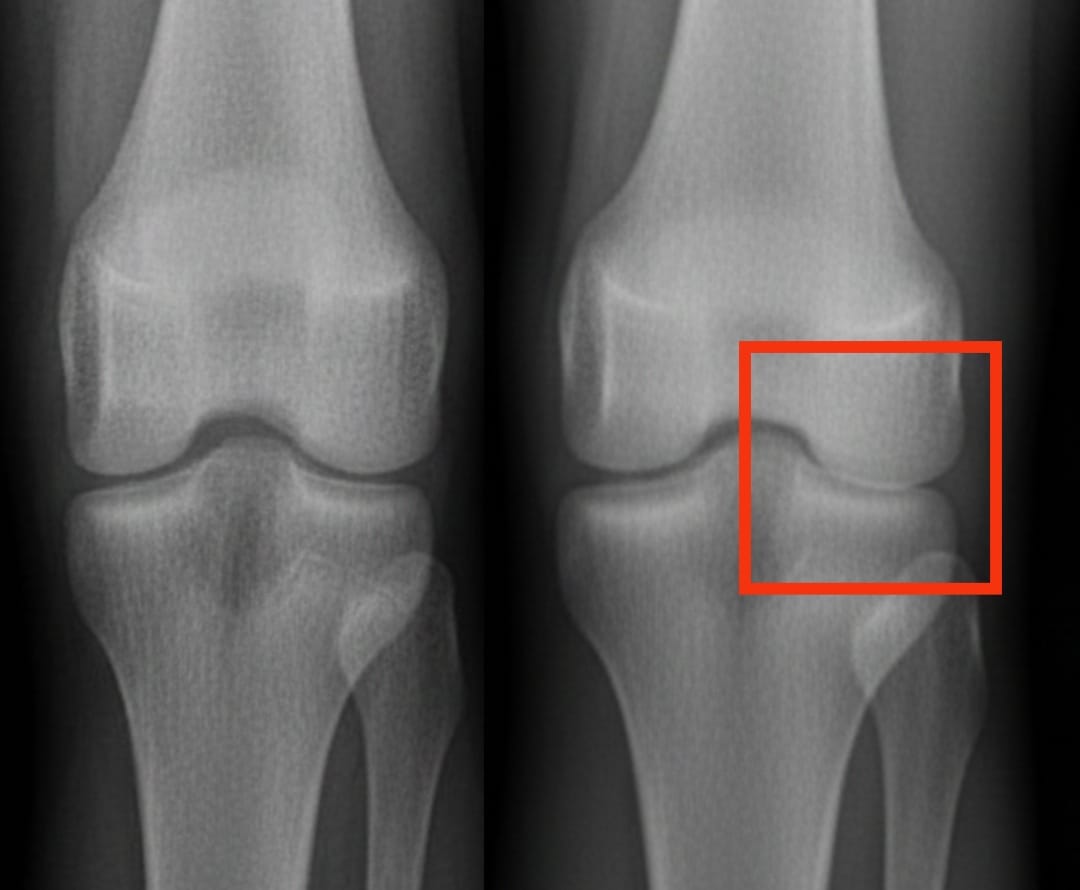

Osteoartritis lutut memengaruhi ratusan juta orang di seluruh dunia. Penyakit ini ditandai dengan keausan bertahap pada tulang rawan, yang menyebabkan nyeri dan kesulitan bergerak. Di antara solusi yang ditawarkan, injeksi plasma kaya trombosit semakin menarik perhatian. Perawatan ini menggunakan darah pasien sendiri yang dikonsentrasikan trombositnya untuk merangsang perbaikan jaringan dan mengurangi peradangan.

Analisis terbaru membandingkan efektivitas plasma kaya trombosit dengan injeksi umum lainnya: asam hialuronat, kortikosteroid, dan plasebo salin. Hasil menunjukkan bahwa plasma kaya trombosit secara signifikan memperbaiki nyeri dan mobilitas setelah enam bulan, dengan manfaat yang bertahan hingga satu tahun. Perbaikan ini lebih jelas dibandingkan dengan yang diperoleh dari asam hialuronat atau kortikosteroid, dan jauh lebih baik daripada plasebo.